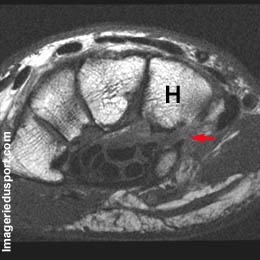

A - IRM du poignet vue axiale T1 : Solution de continuité large au niveau de la base de l'apophyse de l'Hamatum (os crochu). Sclérose des berges fracturaires.

B - IRM du poignet coupe axiale T2 : Signal liquidien au niveau de la zone de pseudarthrose sans remaniement sous chondral associé au niveau des berges fracturaires.

Pseudarthrose large de l'apophyse unciforme de l'Os crochu ou Hamatum.